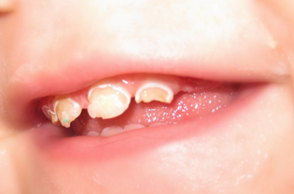

Razvojni defekti se razvijaju i na bočnim zubim i ponekad je i za stručnjaka teško da ih primeti.(slika 5.). Na ovakve defekte se često nadovezuje karijes.

Razvojni defekt gleđi na bočnim mlečnim zubima koji se teško uočavaju i često brkaju sa karijesom.

Razvojne promene na mlečnim zubima treba otkriti što je ranije moguće. Zbog toga su, između ostalog, veoma značajni prvi pregledi već u pvoj godini života. Deca sa razvojnim defektima zubne gleđi spadaju u VEOMA RIZIČNU GRUPU jer su takvi zubi skloniji karijesu, ali i trošenju, pa je neophodna hitno preduzeti dodatnu zaštitu i jačanje. U nekim slučajevima jedino rešenje da se sačuvaju zubi je i postava fabričkih krunica.